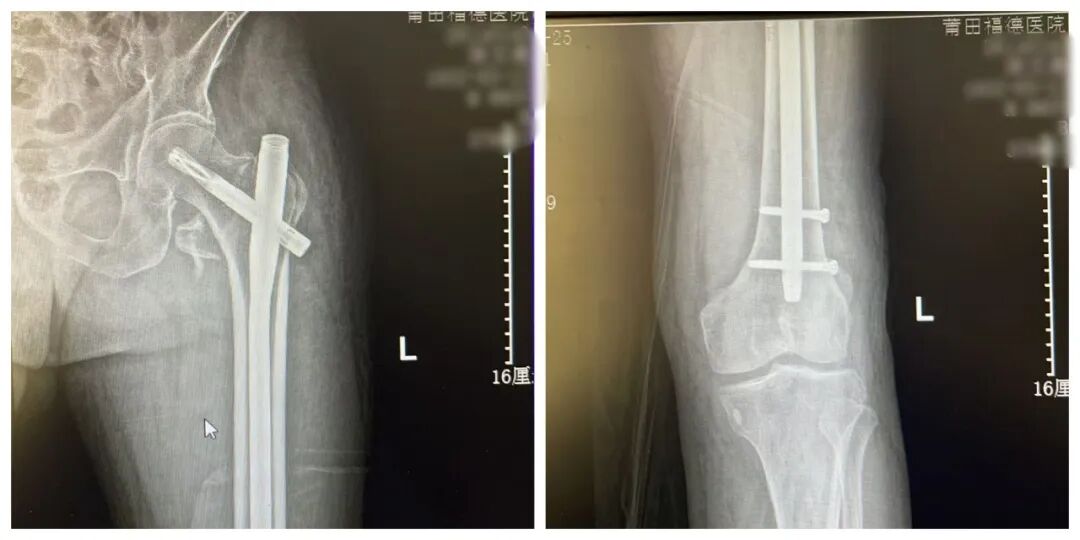

患者术后影像

尽管 患者高龄 给手术带来了不小压力,但骨科手术团队凭借精湛医术和丰富经验,顺利完成了手术。术后复查DR,提示 金属内固定在位,断端对位良好。